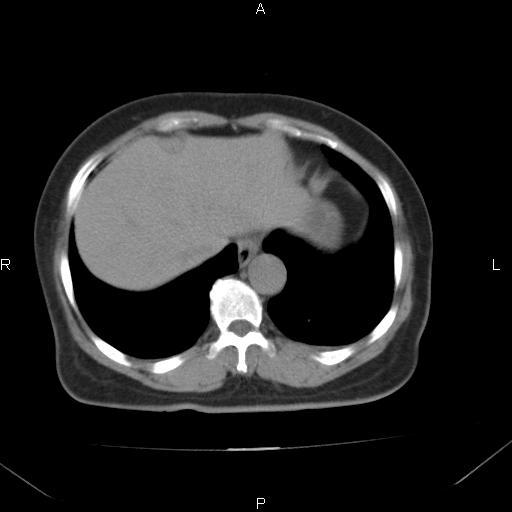

女、63Y 双眼睑下垂,早轻晚重。 胸腺瘤???

结果胸腺瘤